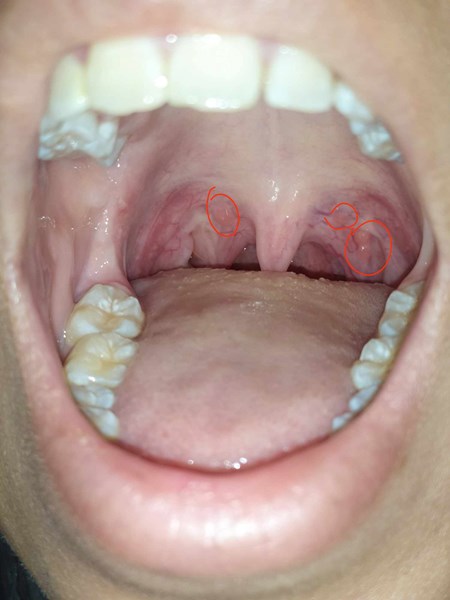

Alguien sabe que son? :0 se ven como granitos

Me salieron hace poco, pero no se que son :0 se ven medio rojas pero las acabo de notar

Desde la ignorancia opino que podría tratarse de una amigdalitis bacteriana y, sobre todo diría que se asemeja a alguna clase de calculo amigdalino, ("semi plano" en su caso), que no reviste en principio ningún riesgo o problema. Aquí podría ver si lo desea su aspecto y un poco de información,

Si existiera una probabilidad de que se trate de un absceso en la parte posterior de la garganta, es necesario de preferencia acudir a un médico (de cabecera o especialista familiar), porque un absceso periamigdalino que no se reduce por sí mismo y se deja sin tratar puede evolucionar dando lugar a posibles complicaciones siempre poniéndonos en un escenario negativo, creo que en principio, en caso de no remitir la inflamación por sí sóla, es preferible no arriesgar.

Por otro lado, un Eritema gingival lineal en fase inicial o un comienzo de gingivítis también podría ser osible, pero sin duda debe atenderle un profesional,